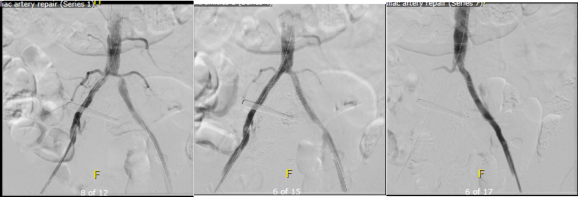

The hardest case that I have taken care of ever was at the Clinic a couple of years ago. The patient was a middle aged man who had ruptured an aortic aneurysm in another state some months prior and had undergone a repair complicated by a pancreatic injury along with some enterotomies resulting in a graft infection along with high output pancreatic and enteric fistulae from an open abdomen. He arrived cachectic, in septic shock and had a pseudoaneurysm from the distal anastomosis of a short tube graft. I immediately took him to the OR to place a stent graft across the pseudoaneurysm neck to prevent rupture and placed him on TPN to correct his cachexia. The abscesses and hematomata were drained percutaneously, and an effort was made to control the fistula with a heroic effort on the part of the ostomy team. He turned around and was able go to an LTAC on TPN and antibiotics. There he gained twenty pounds and returned flush and active. Stage two was three months later and done to replace the still infected grafts with cryopreserved homograft. I did this via a right retroperitoneal approach as the left side and abdomen were a mess from the inflammation. After I removed the grafts and sewed in the homograft, general surgery reorganized his bowel and discovered that he only had about 30cm of useable small bowel and would be on TPN for life. But he was alive and learning to walk again, and eventually came back 6 months later for follow-up and gave me a hug.